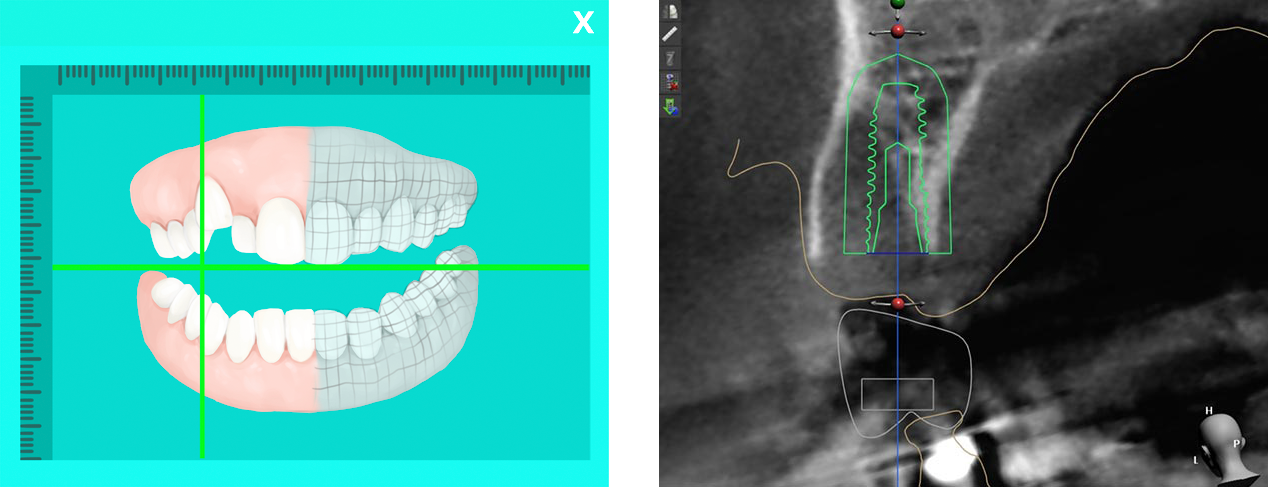

3차원 CT 이미지와 컴퓨터 모의 시술 기법을 통해 환자 턱뼈에 보다 정확한 위치에 식립하는 시술 방법으로, 시술 전 미리 위험 요소를 피할 수 있습니다. 잇몸에 작은 구멍만 뚫어 진행되기 때문에 큰 절개 없이 최소 통증으로 시술 받으실 수 있습니다. 동탄주치과에서는 Osstem Oneguide 분석 시스템을 통한 네비게이션 임플란트를 시행하고 있습니다.

구강 상태를 그대로 재현하여 3D CT를 이용한 모의 수술을 진행합니다.